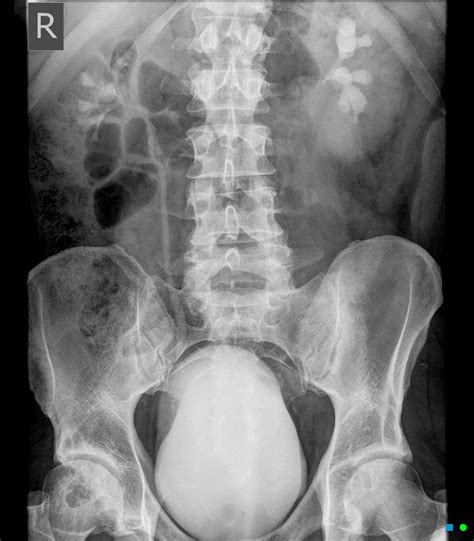

A Kub Abdominal X Ray, also known as a KUB (Kidneys, Ureters, Bladder) X-ray, is a type of abdominal radiograph that provides a detailed view of the abdominal cavity. This imaging technique is commonly used to assess the organs and structures within the abdomen, including the kidneys, ureters, bladder, intestines, and other soft tissues. The primary goal of a Kub Abdominal X Ray is to detect abnormalities such as obstructions, infections, or tumors.

Interpreting the results of a Kub Abdominal X Ray requires expertise in radiology. The radiologist will look for various signs and abnormalities, including:

• Air or gas patterns in the intestines

• Abnormalities in the shape or size of organs